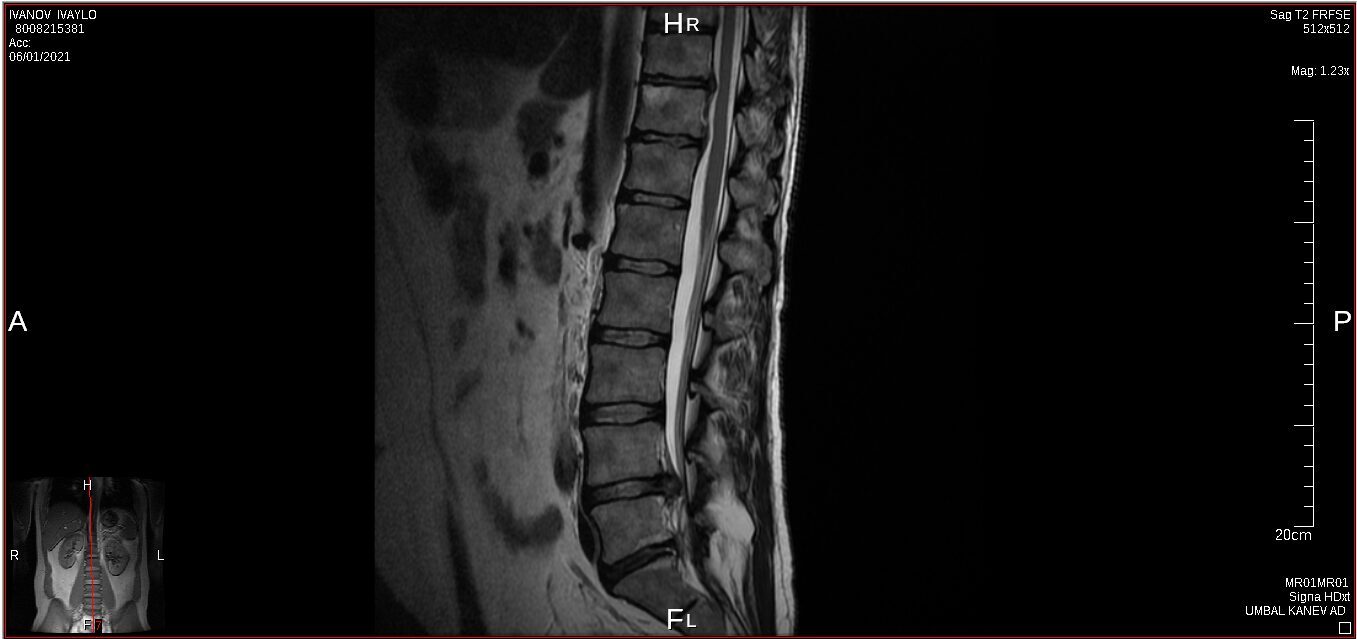

I have a lower spine problem, herniated disk and was using acupuncture (acupuncture is really good to control your musculus and controlling you like a robot) treatments with a Chinese doctor, first time all was perfect, but second time looks like happen mistake, you will be able to see this on pictures from private MRI scan– nuclear magnetic resonance that I have organised for myself. My left leg was just bone and skin, I lost all the musculus, because was not able to feed the main nerve responsible for keeping the proper function of the whole leg – I was parallelized. Pain is 24/7, 10 out of 10. At Royal infirmary hospital Edinburgh where I was hospitalized was giving me crazy amount of pain killers and very strong, that never helped. The doctors at the hospital they did great job providing me with modern technology to prevent the rest of the disk to slipping out to obtain the so-called calcification. All NHS staff did great job looking after me there. By 98% of the Doctors from around the world that I have managed to contact told me, that I have to make operation and there is no chance this to be sorted out other way. Well I have spent six months from my life and thanks god I had the finance to do that, trying to avoid operation. I have meet the right people to help me and expand my knowledge and I managed to avoid operation. Thanks to nature too. This situation get me to start learning a lot for human being anatomy and physiology, also reflexology, trigger points, blood, tocsins, minerals, how brain is responsible and reacting and much more…